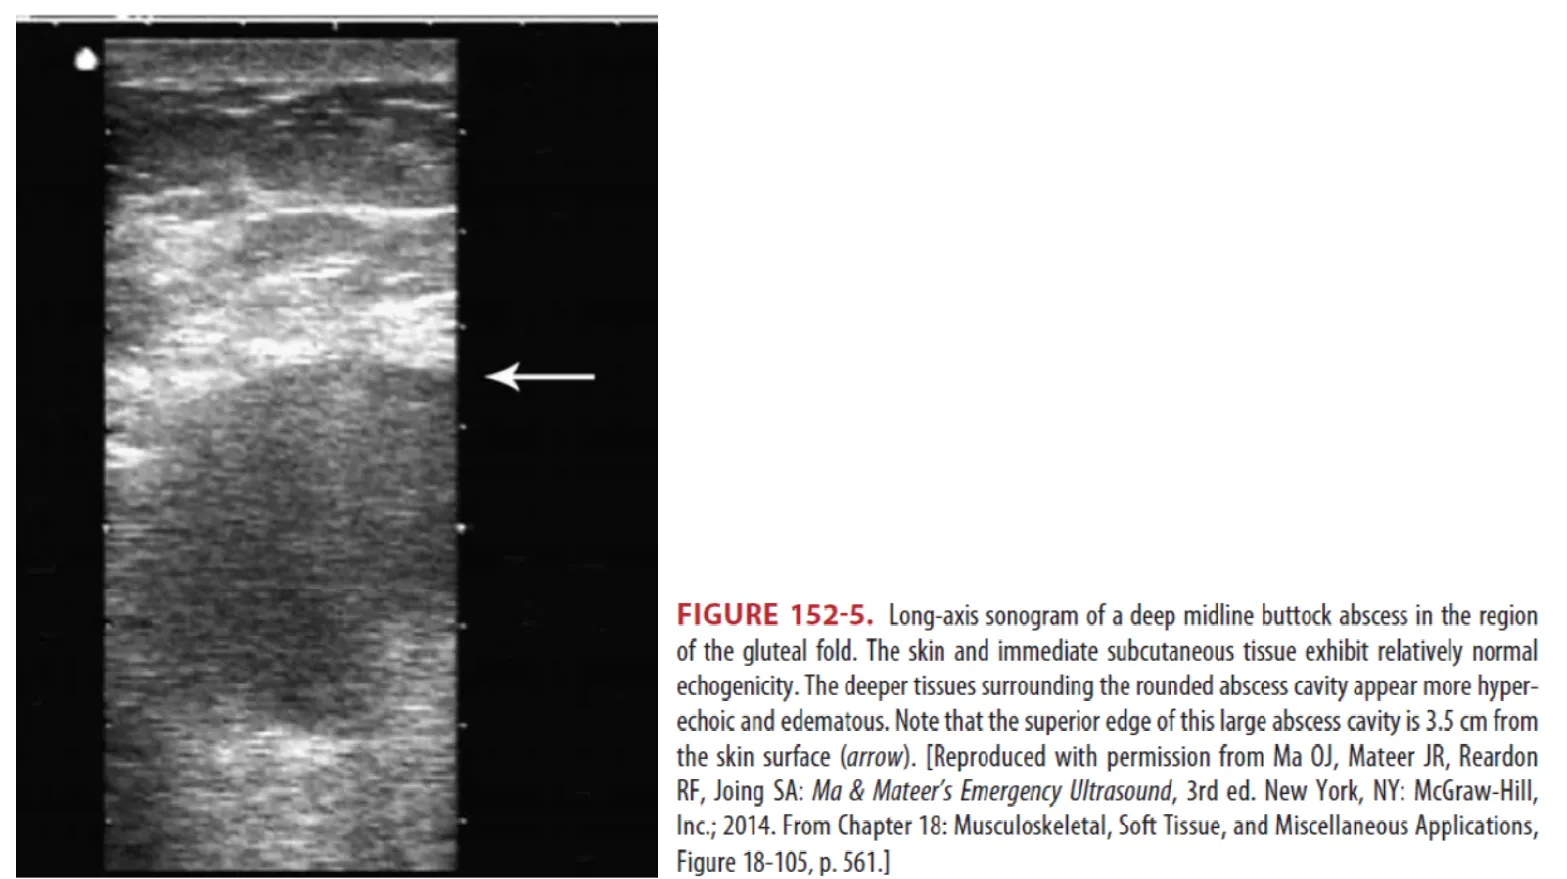

(2) POCUS

: Deep abscess와 cellulitis를 구별하고 abscess 내 이물질을 찾거나 drainage의 적절성을 결정하는데 중요함 (Fig. 152-5)